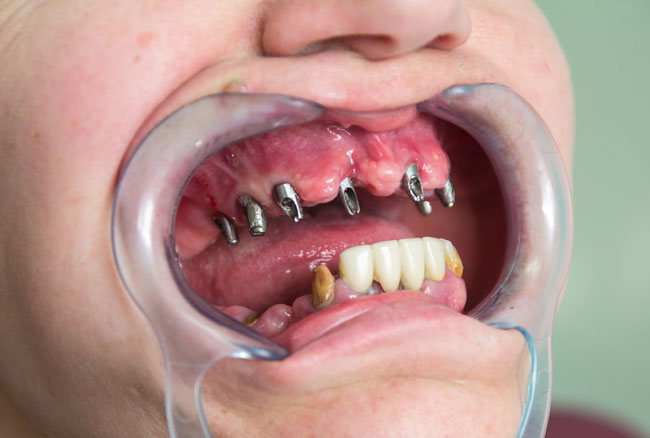

In 02.05.2014 the second stage of rehabilitation was made. Revealed endosseous part 6 Alpha Dent implants in the upper jaw were opened, gums conditioners installed and restored abutment of 15-years old implant in 1.5 using titanium cap. The success rate of implantation in the rehabilitation of patient P. with edentulous maxilla reached 100% (see Fig. 4, 5).

Maxilla prosthetics for patient P. with fabrication of cermet bridge held as follows: